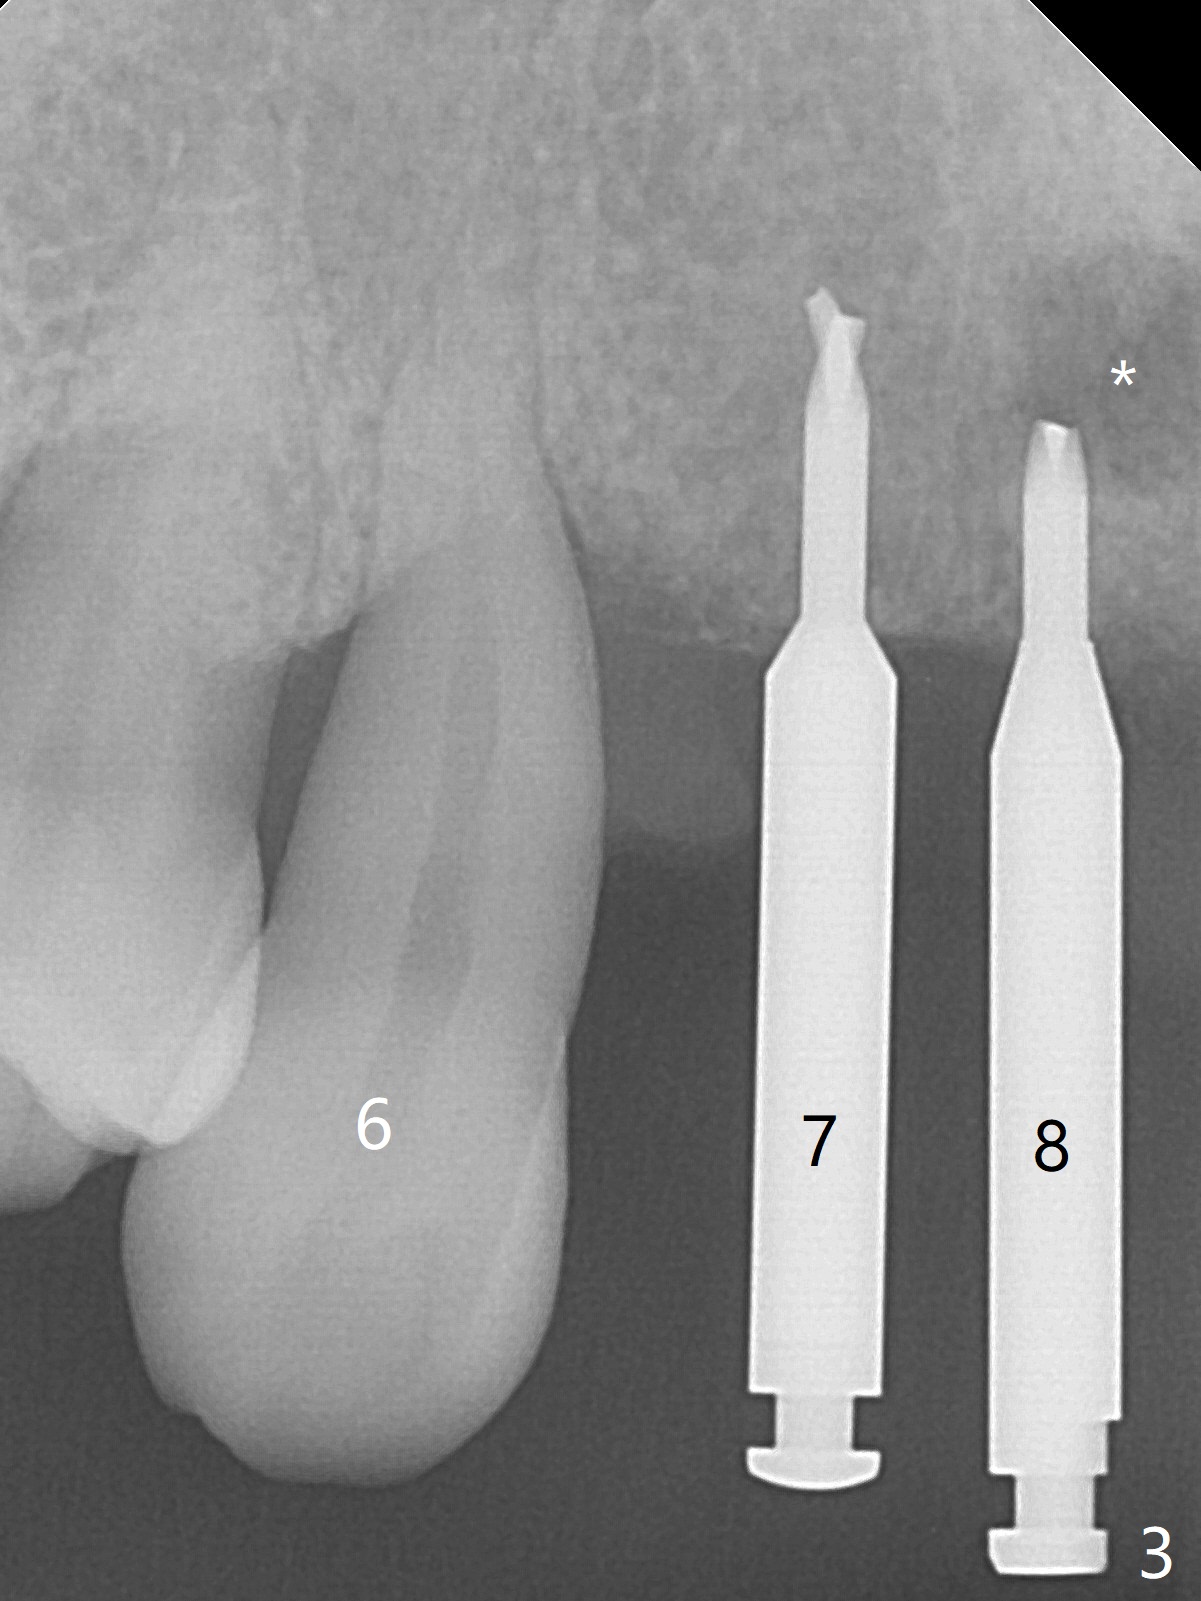

Although the ridge of the maxillary anterior ridge looks moderate in width (Fig.1), the bone is ~4 mm buccopalatally. Suction down surgical stent (Fig.2') made from the lab-fabricated provisional (Fig.2) will be used to check the position and trajectory of osteotomies. PAs taken after initial osteotomies (1.2 mm drill) show those at the central incisors tend to be mesial (close to the Incisive Canal *), while those at the lateral incisor sites distal (Fig.3,4). After adjustment, the position and trajectory of the osteotomies are acceptable (Fig.5,6). To reduce the chance of perforating the Incisive Canal (Fig.3,4 *), 2.5 mm 1-piece implants are inserted with >40 Ncm (Fig.7,8). After deep placement of the implants, Vanilla graft is placed at the crest (Fig.9,10 *). An immediate splinted provisional is fabricated from the suction down stent. The gingiva is healthy around the provisional (Fig.11) and the implants (Fig.12,13) 1 month postop. The provisional is adjusted monthly so that the interdental papillae can be elongated. No bone resorption is observed 6 months postop (Fig.14,15). Crowns are cemented 8 months postop (Fig.16-18). The keratinized gingiva appears to have formed the abutments 8 months postop immediately pre-cementation (Fig.19).